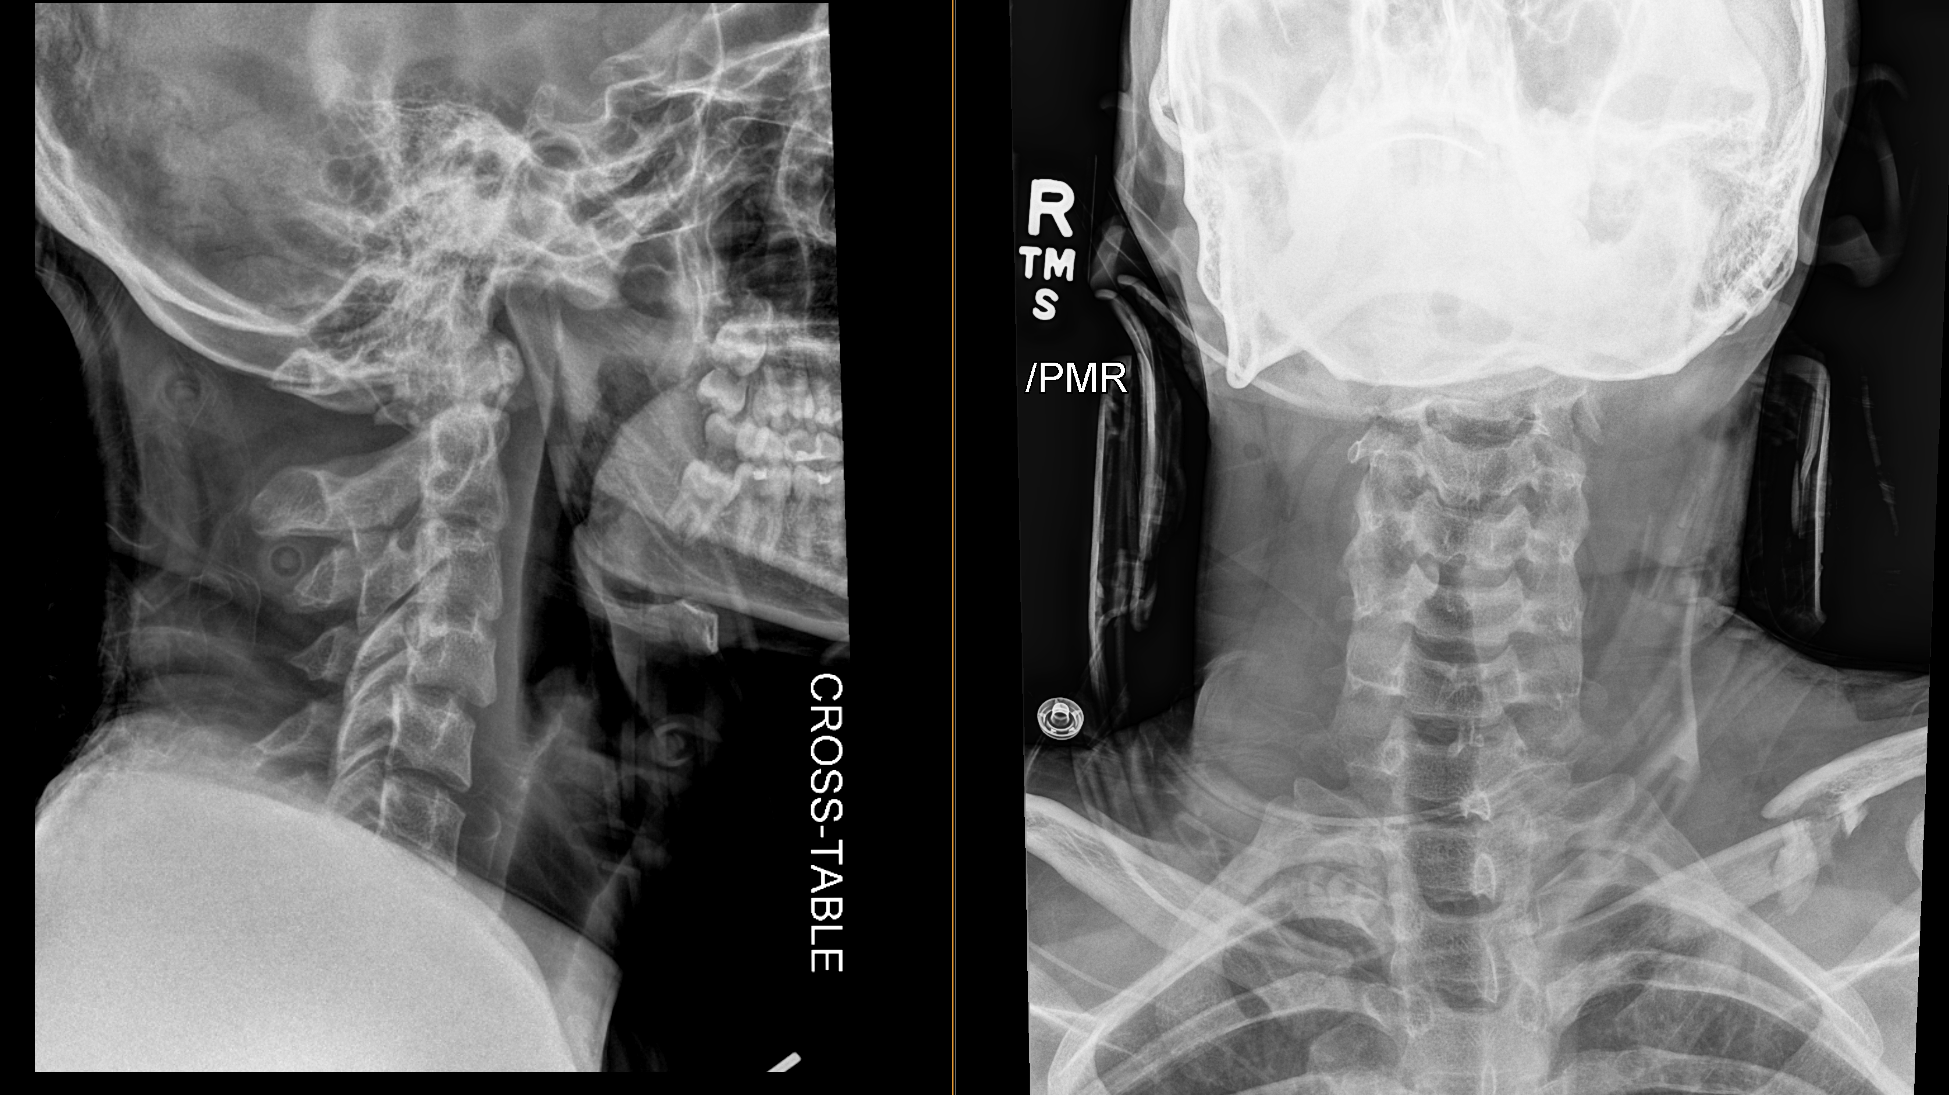

XR Cervical Spine AP and Lateral

There is prevertebral soft tissue swelling.

No, there is no prevertebral soft tissue swelling. This does not preclude injury to the cervical spine.

Radiographs are often obtained as the initial study particularly when the patient is still in a collar. If the exam adequately covers the cervical spine and C7-T1 junction and no abnormality is seen, the collar may be removed and further imaging obtained if symptoms persist. Many institutions obtain the CT scan as the initial exam. In this case, the radiographs were obtained first.